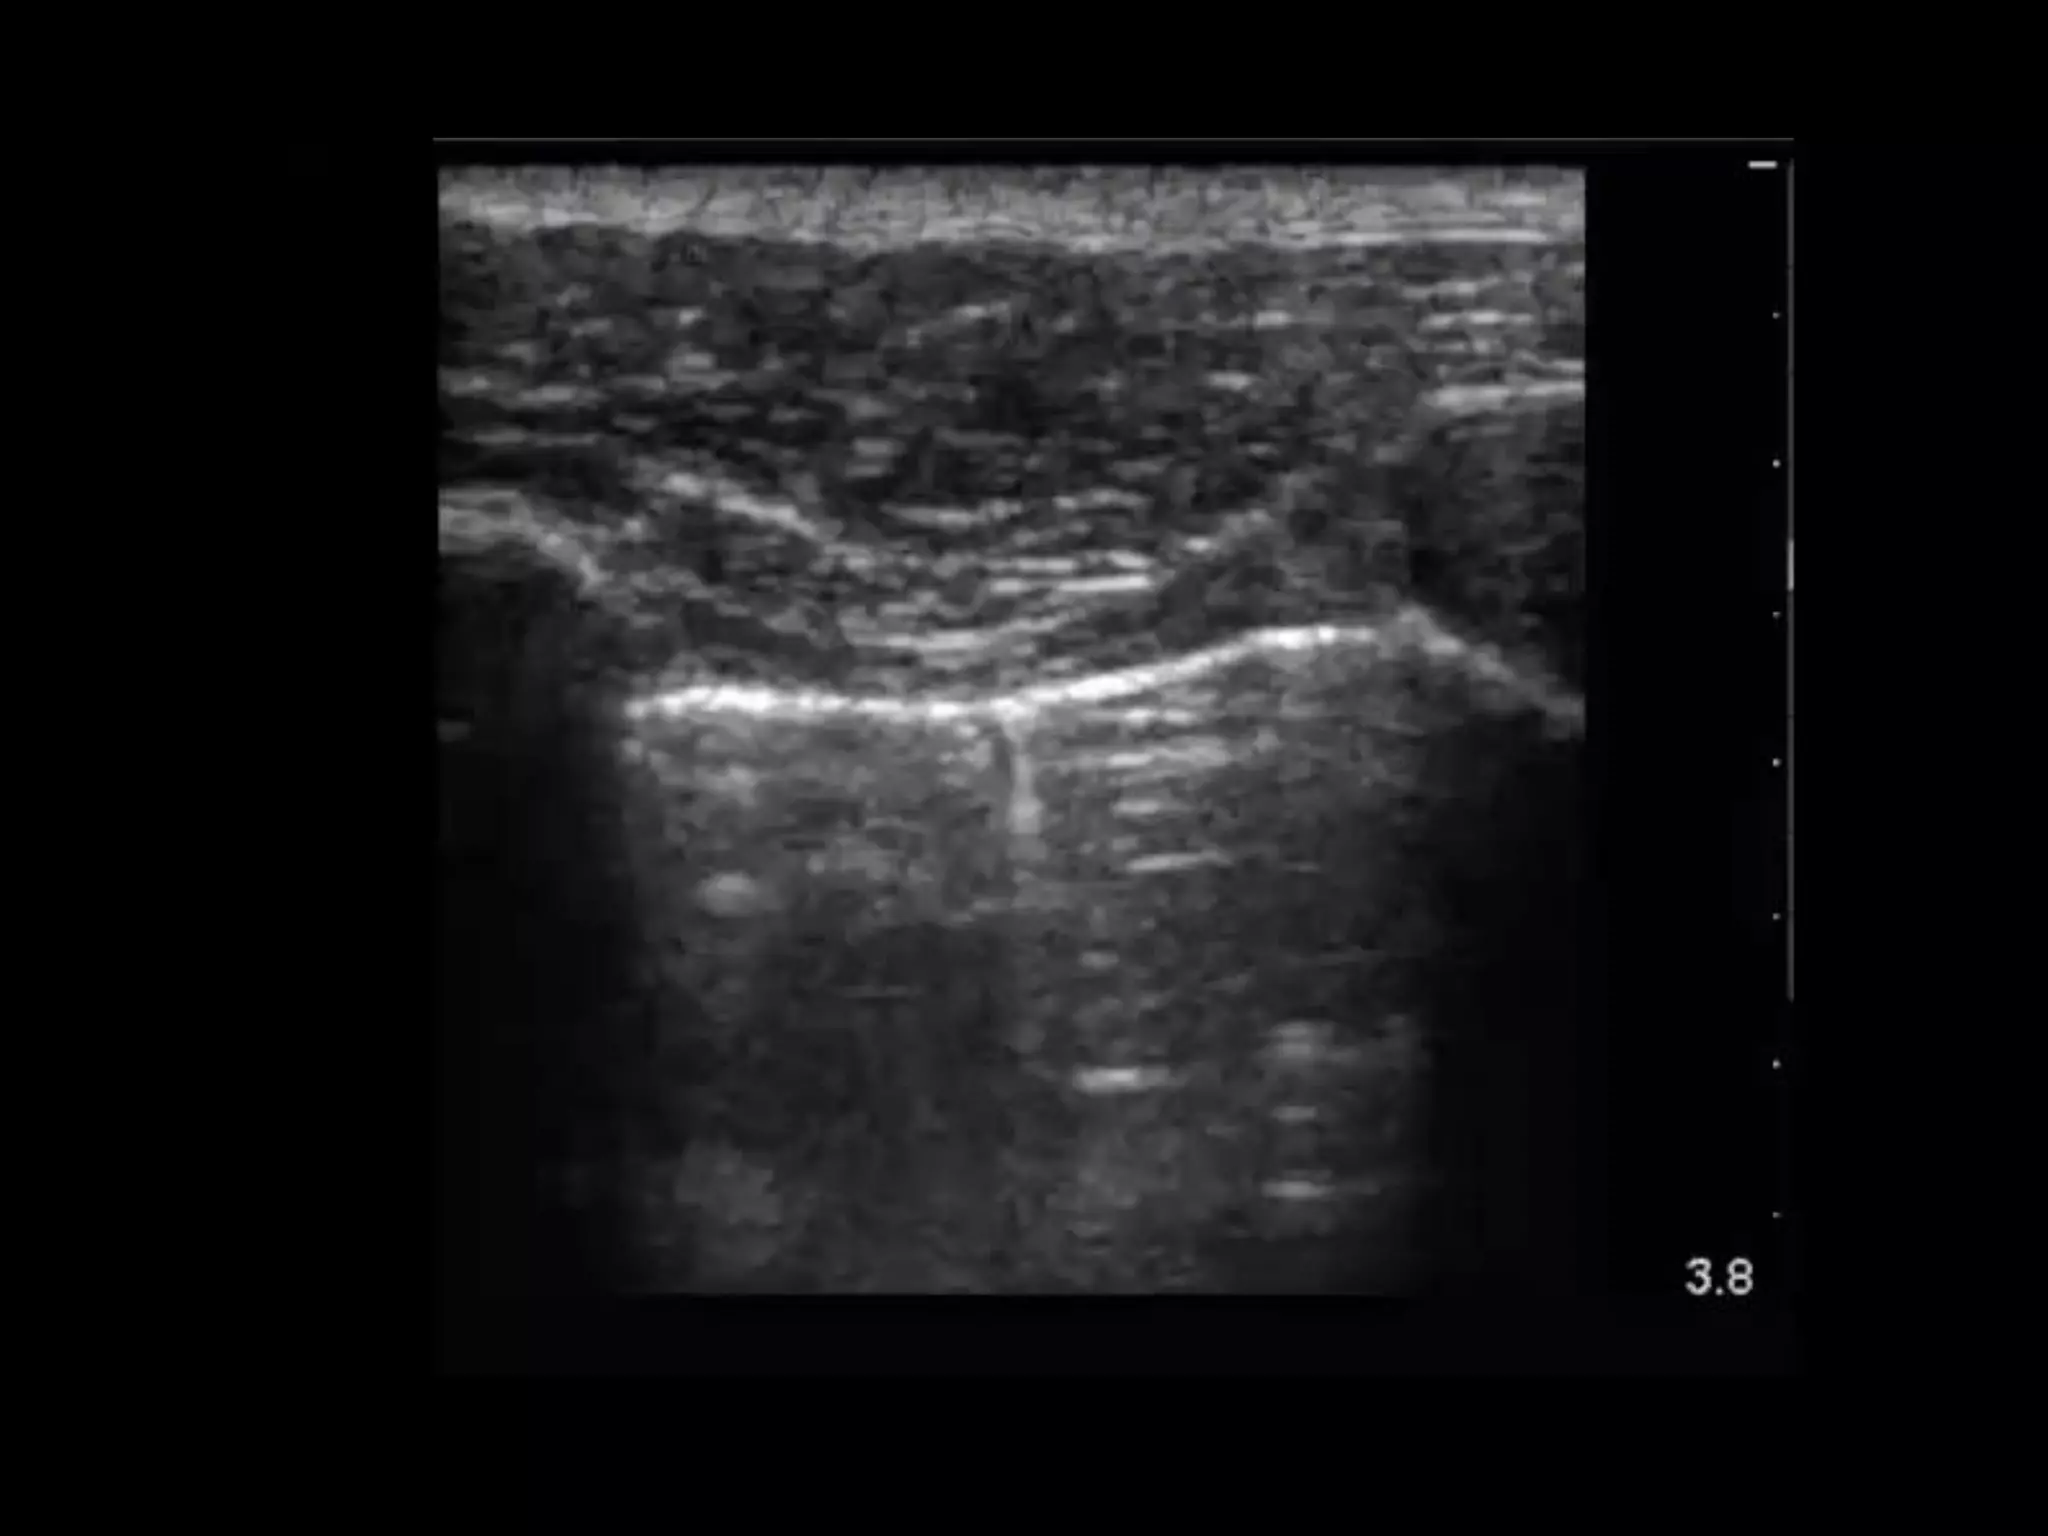

Subcutanous emphysema

• There is air lying between the facial planes

• No ribs are seen

• This is surgical emphysema obscuring true

interpretation of the underlying lung